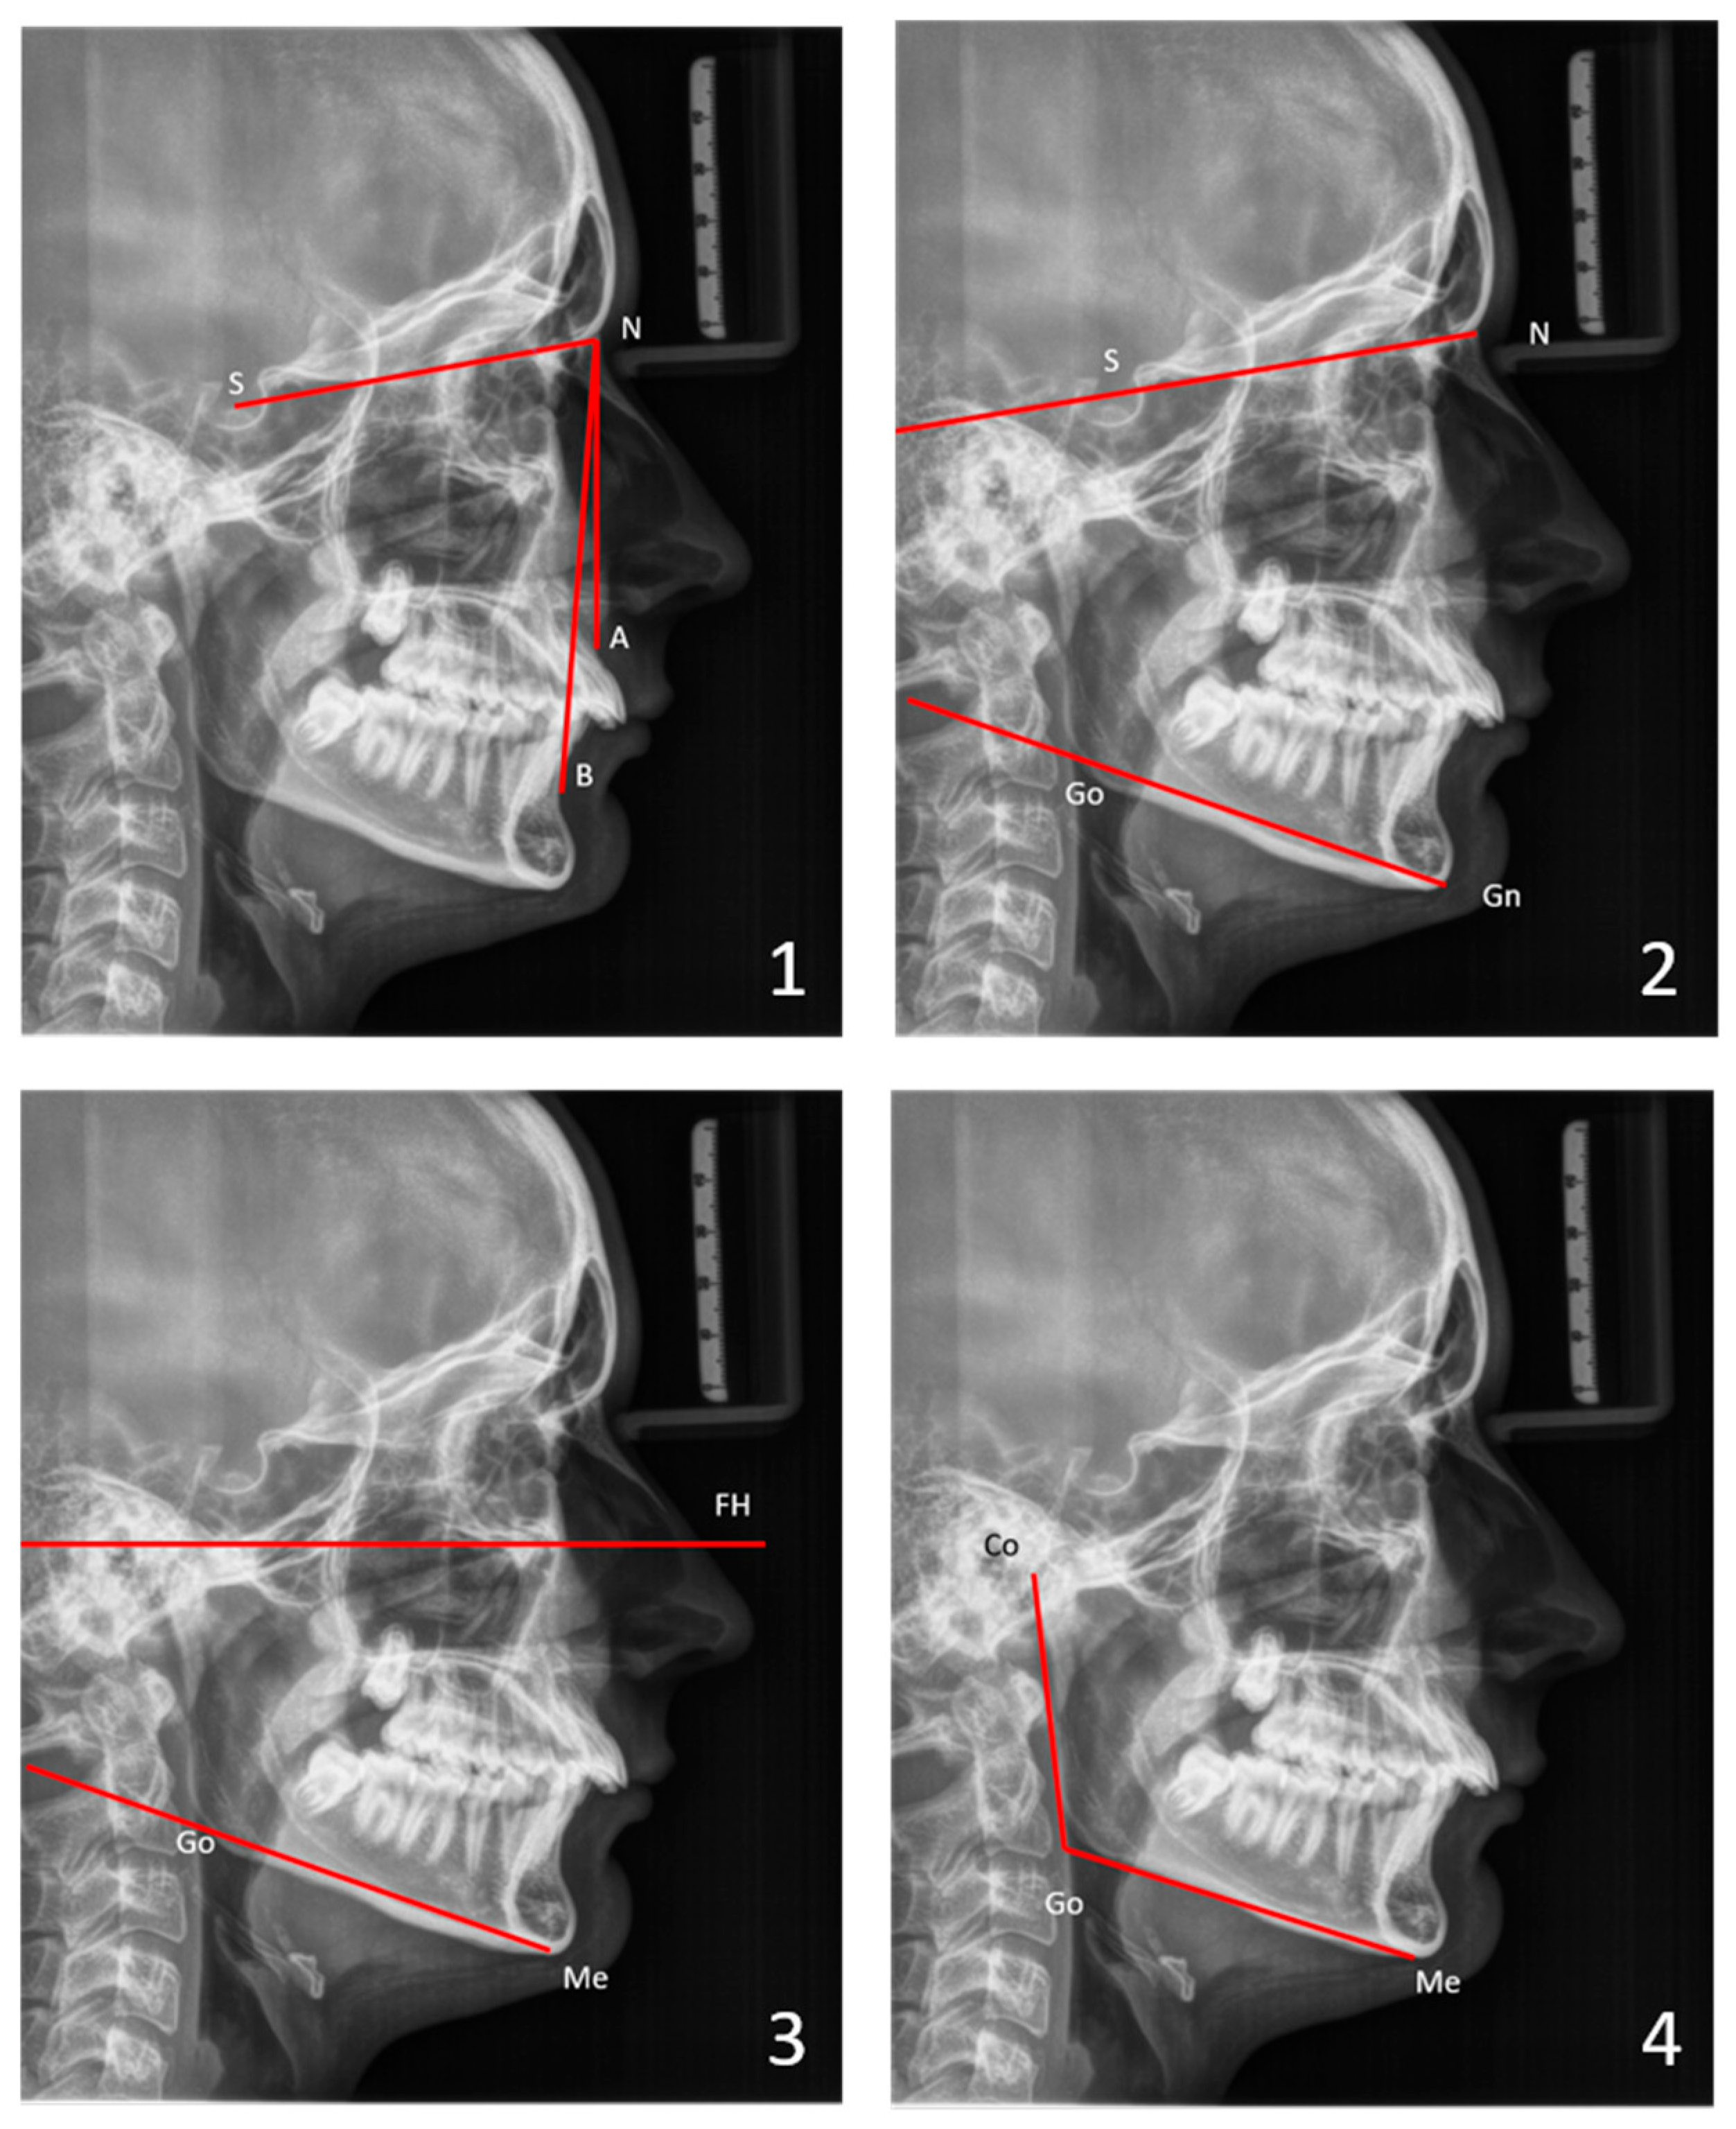

For the skeletal cephalometric analysis (a simplified analysis according to Tweed [35]), the sagittal positions of the maxilla (SNA) and the mandible (SNB) in relation to the cranial base, as well as their relative position to each other (ANB), were determined. Vertical parameters, such as the facial plane divergence (SN-GoGn angle), the FH plane–mandibular plane angle (FMA), and the gonial angle (CoGoMe), were considered to quantify the facial divergence (Figure 2). See the Appendix A for definitions of landmarks and angles.

Mandibular width was determined by measuring the distance between the two antegonial notches on frontal cephalometric radiographs. Age-dependent reference values were used for this analysis (analysis according to Ricketts [38]) (Figure 5).

Facial and mandibular growth was studied in patients who had two cephalometric radiographs taken with an interval of at least 2 years. Skeletal sagittal parameters (SNA, SNB, ANB angles) and vertical parameters, such as the facial plane divergence (SN-GoGn angle), the FH plane–mandibular plane angle (FMA), and the gonial angle (CoGoMe), were determined. Additionally, the Z angle from soft-tissue analysis was used to evaluate the convexity of the lower facial profile during growth (see the Appendix A for definitions).